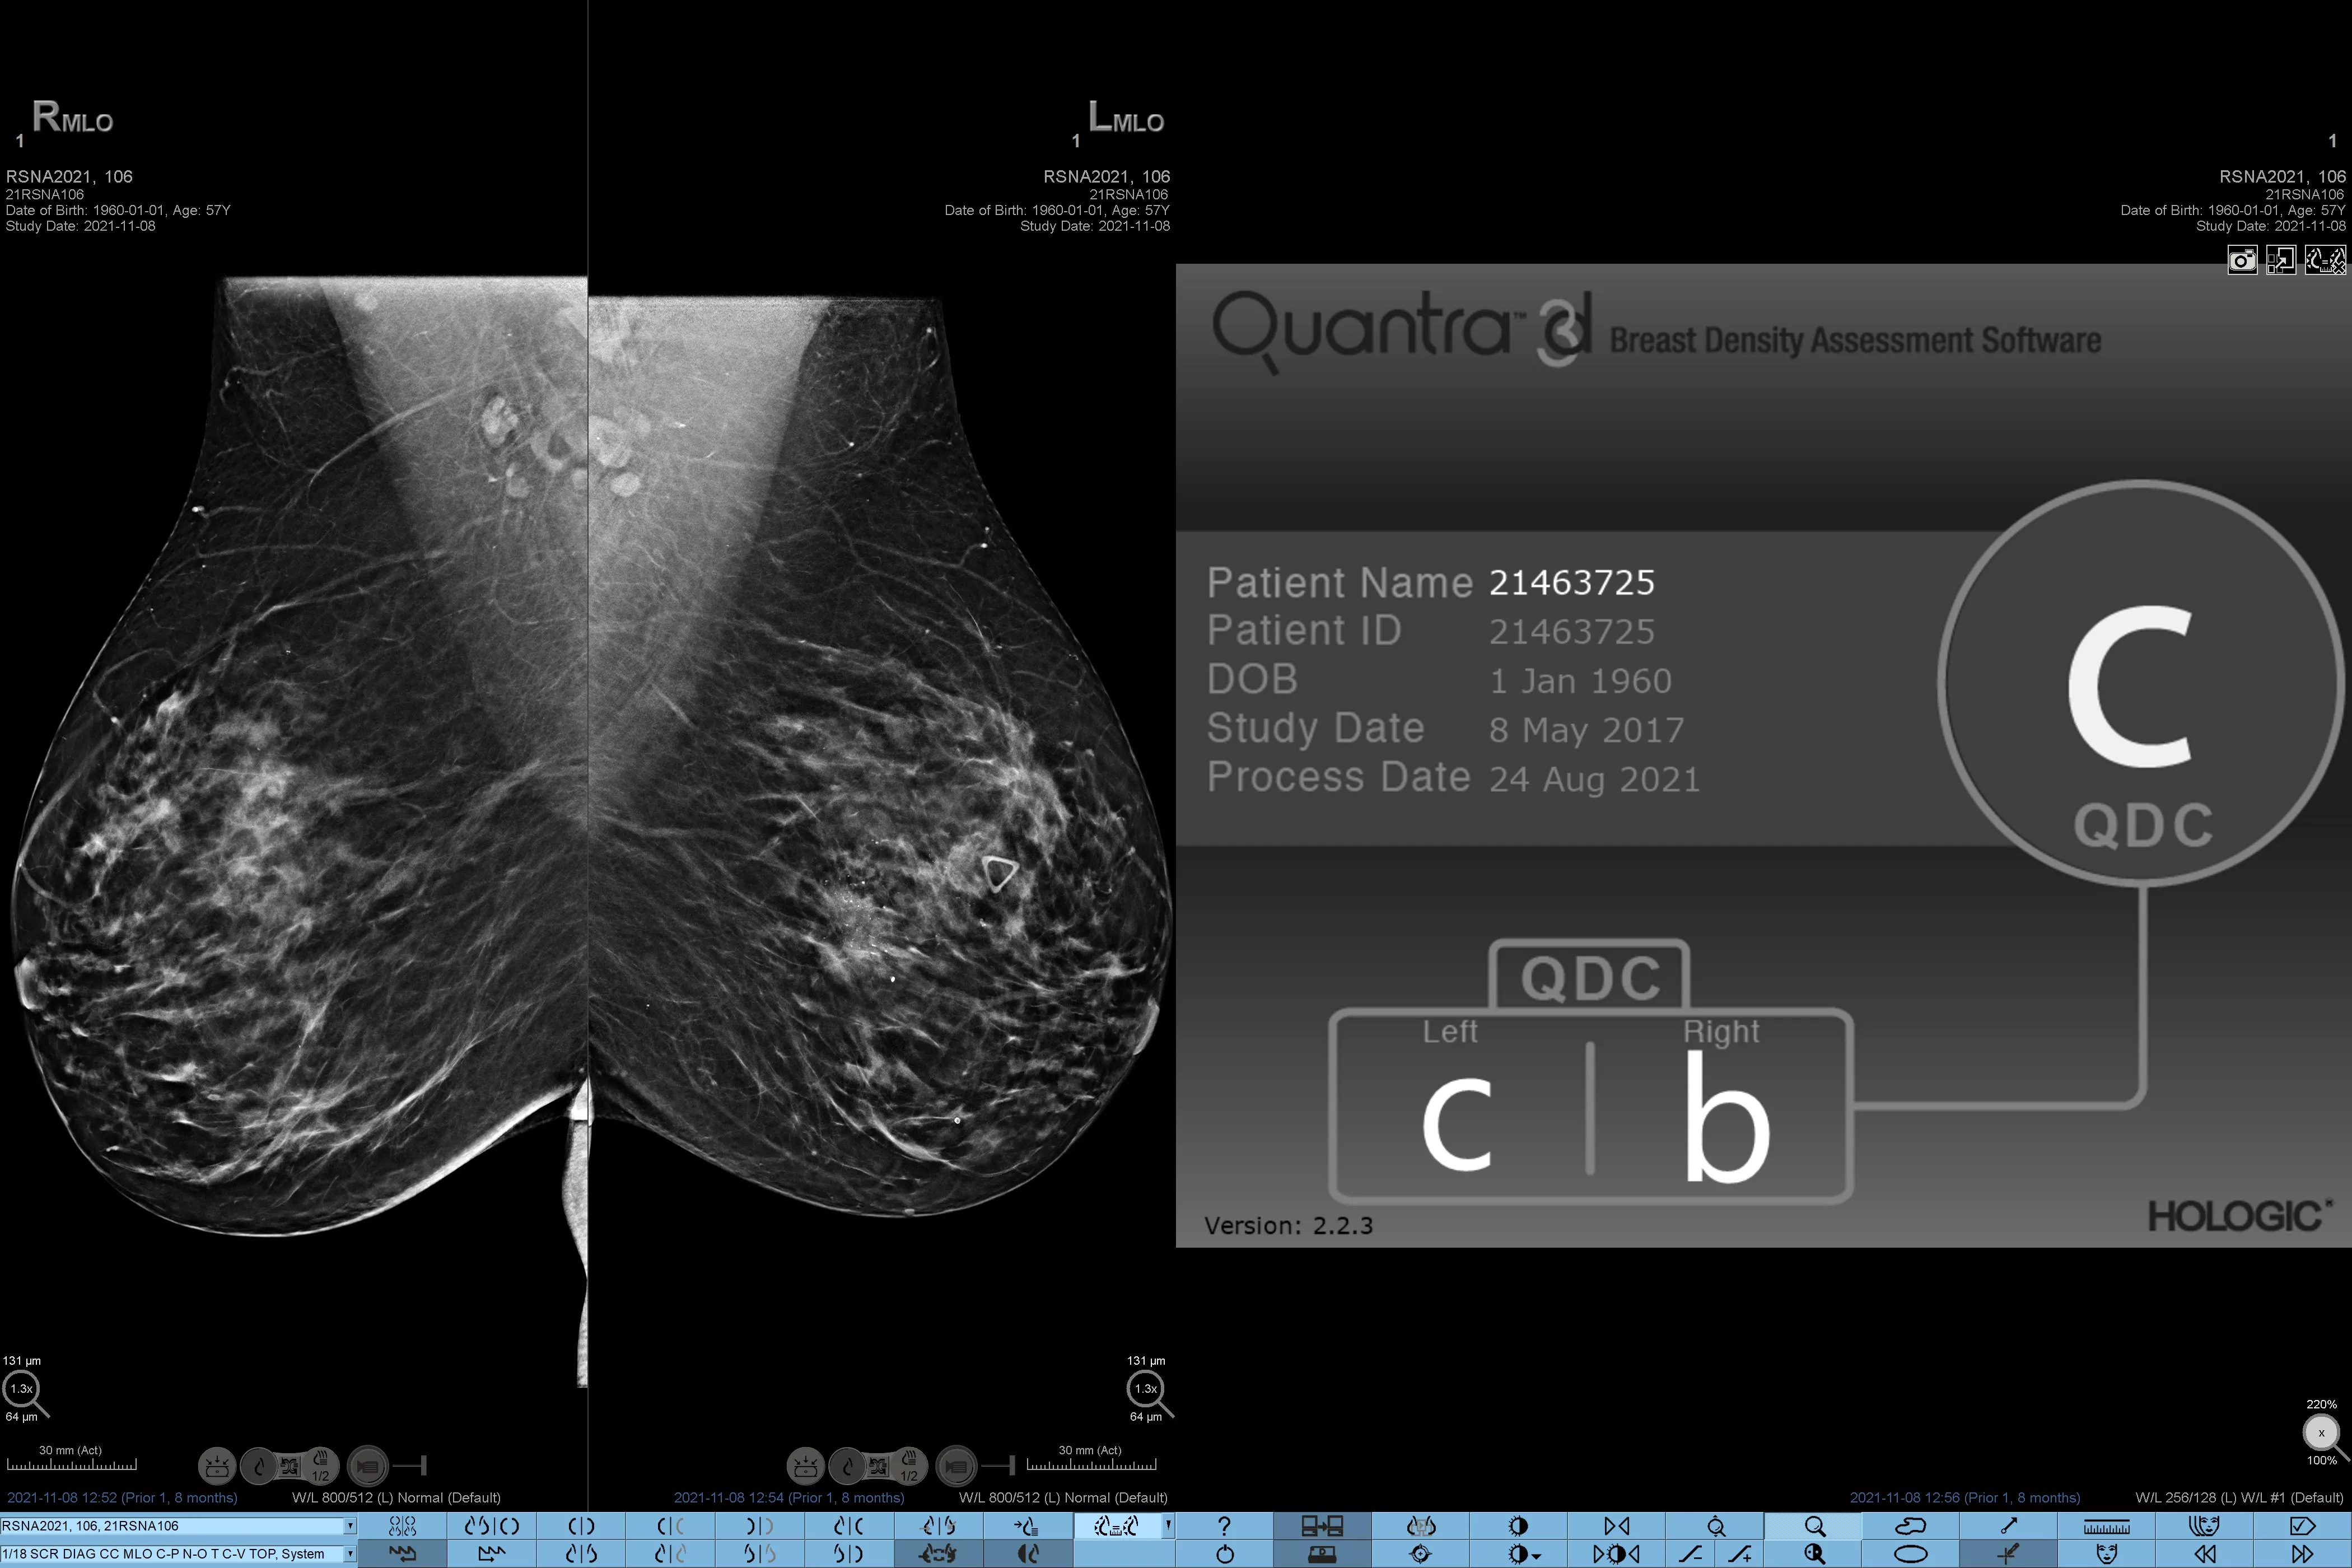

Higher breast density is known to increase a woman’s risk for breast cancer.1 The need for accurate, unbiased analysis is therefore critical. Powered by machine learning, Quantra technology software analyses both 2D™ and tomosynthesis images for distribution and texture of parenchymal tissue. It categorises breasts in four breast composition categories consistent with guidance from the American College of Radiology (ACR) BI-RADS Atlas 5th Edition.2

In addition to volume, pattern and texture of fibroglandular tissue may play just as an important role in mammographic cancer risk prediction.3-5 By analysing and categorising breast texture and pattern, our technology can deliver the accurate information you need to achieve more consistent and reliable scoring and confidently design patient-specific screening.

Objective machine learning algorithm that assigns breast density category based on analysis of breast tissue texture and patterns.

Quantra software’s unbiased algorithm analyse both 2D and tomosynthesis images to support your analysis by:

• Overcoming subjectivity in visual assessment, providing more consistent, and more reliable scoring.*